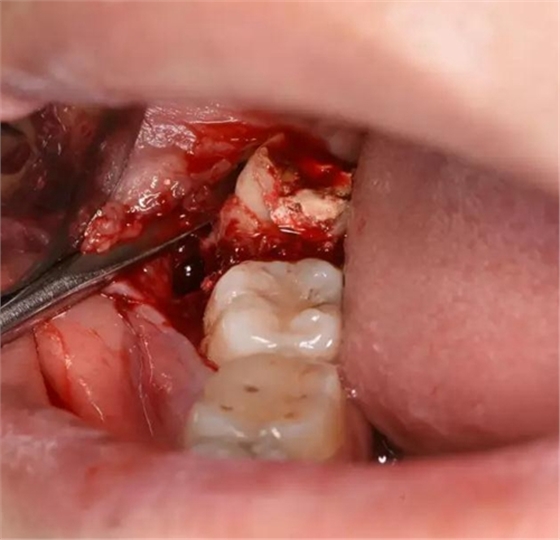

圖7.骨膜剝離器翻開(kāi)牙齦、暴露48合面

圖8.近中放置牙挺、挺松48